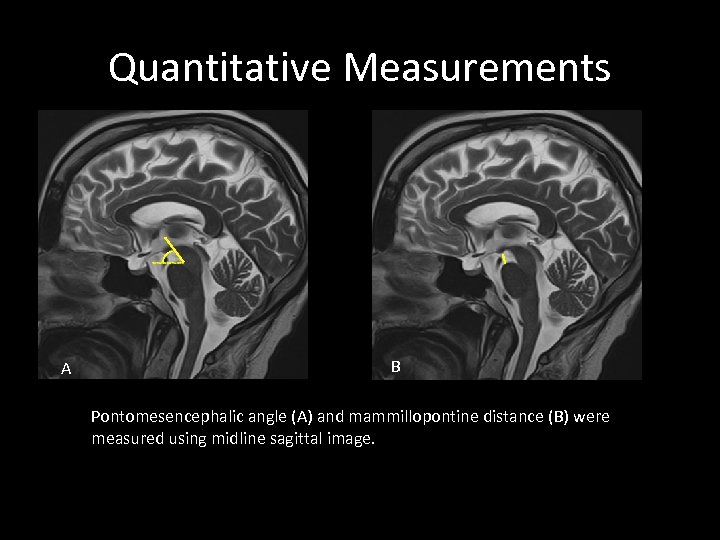

Quantitative Measurements A B Pontomesencephalic angle (A) and mammillopontine distance (B) were measured using midline sagittal image.

Quantitative Measurements A B Pontomesencephalic angle (A) and mammillopontine distance (B) were measured using midline sagittal image.